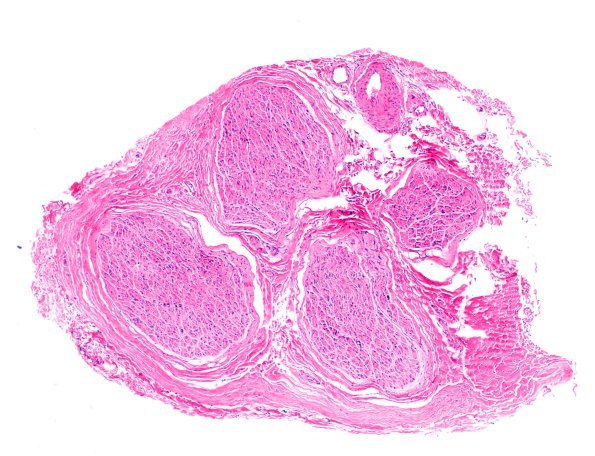

Washington University Experience | PERIPHERAL NEUROPATHY | 12 ANTI-MAG NEUROPATHY | 4A1 (Case 4) H&E 4X 1

Case 4 History ---- A 69-year-old man with a severe demyelinating polyneuropathy in the setting of MYD88 positive lymphoplasmacytic lymphoma. ---- 4A1,2 There is no evidence of an inflammatory infiltrate. Although H&E sections are not reliable to determine axon number, the pallor of the endoneurial contents is suspicious for myelin axon loss. (H&E)